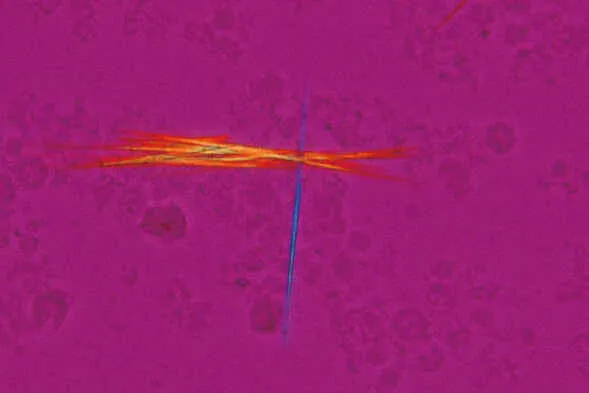

A 45-year-old presents with sudden-onset first metatarsophalangeal joint pain, erythema, and inability to weight-bear. Serum urate is 520 μmol/L, and joint aspiration reveals negatively birefringent needle-shaped crystals-confirming gout . Meanwhile, a 72-year-old with breathlessness has Wells score 6.5 (PE likely); D-dimer is 850 ng/mL, and CTPA confirms segmental pulmonary embolus . These cases demonstrate guideline-concordant diagnostic pathways.

Acute monoarthritis demands rapid differentiation between gout, pseudogout, septic arthritis, and trauma. Septic arthritis is the critical emergency-joint aspiration must occur before antibiotics if feasible. Synovial fluid WCC >50,000/mm³ with neutrophil predominance suggests sepsis, while crystals confirm crystal arthropathy . In anaemia, distinguishing iron deficiency from thalassaemia trait prevents unnecessary iron supplementation: ferritin differentiates, but both cause microcytosis .

| Feature | Gout | Pseudogout | Septic Arthritis |

|---|---|---|---|

| Onset | Hours | Hours-days | Hours |

| Joint | 1st MTP (70%) | Knee (50%) | Any (knee commonest) |

| Crystals | Negative birefringent | Weak positive | None |

| Synovial WCC | 2,000-50,000 | 2,000-50,000 | >50,000 |

| Temperature | Usually afebrile | Usually afebrile | Fever >38°C |